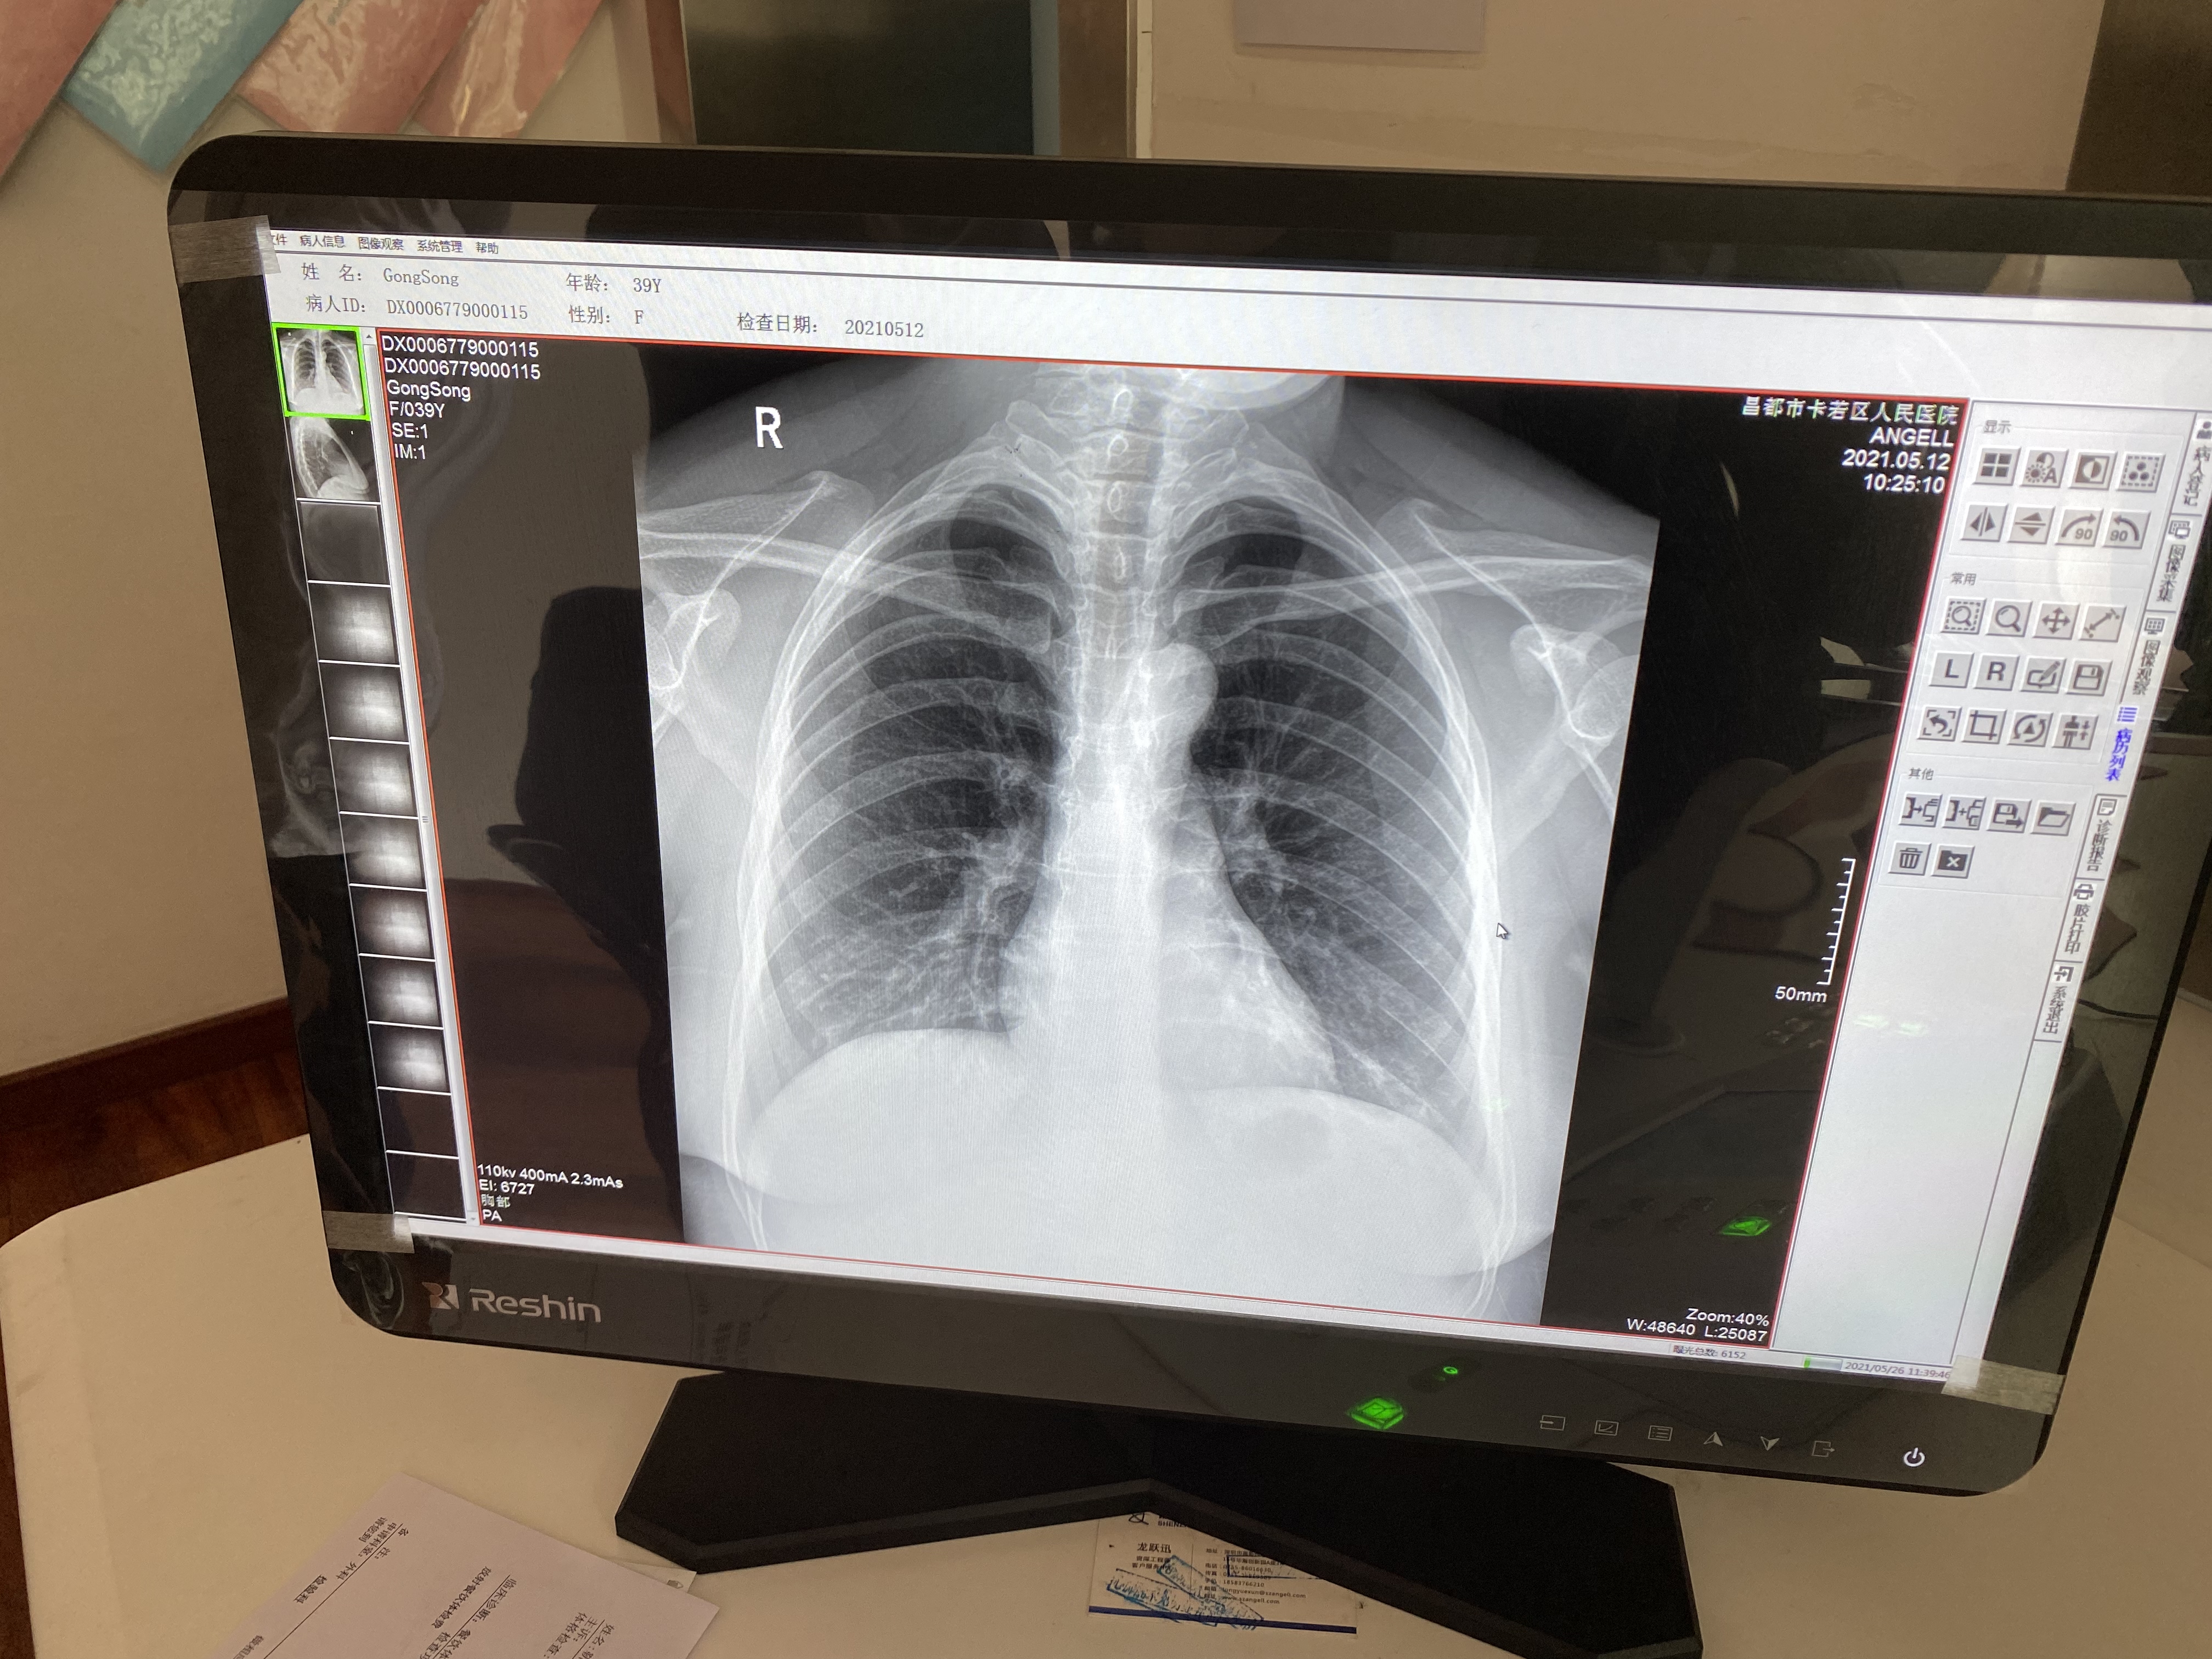

作为一款动态多功能诊断专用DR设备,腾灵支持高清摄片、透视摄影、造影摄影、全脊柱摄影、全下肢摄影检查于一身,满足低人口密度地区的多种数字化X线摄影检查需求。在卡若区人民医院,每天大约有60人左右的检查人次,来自于一区十县 24个镇118乡的藏区百姓,腾灵在过去近一年的服役中赢得了放射科主任及主管技师的一致认可。

“这个设备好得很,现在我们这个医院就1台这个设备,每天都在给病人做检查。摁一下摁扭它就可以立起来,体检病人的时候我们就立起来检查,拍出来的图像很清楚。它也可以横着放,拍腰椎的病人、骨关节的病人,我们摁一下就可以平放摄片。我们现在已经检查了差不多有1多万个病人了,机器没有出现什么问题,工程师也会经常询问设备的情况,这个设备美得很。”操作设备的主管技师说。

目前,卡若区人民医院放射科仅有3名技术与诊断医师,都是昌都本地的藏族年轻人,没有像内地城市的二甲医院放射科进行技术与诊断的分组,在卡若技师也是诊断医师。技师每天既要完成摆位、摄片,同时也要完成阅片与诊断报告的书写,承受着艰巨的检查任务与诊断压力,确保让每一位患者都能得到精准的检查保障。这种情况,在藏区也是普遍的现象,缺少医师是目前藏区医疗服务能力建设中比较急迫的问题。

图6:腾灵的胸片摄片临床影像